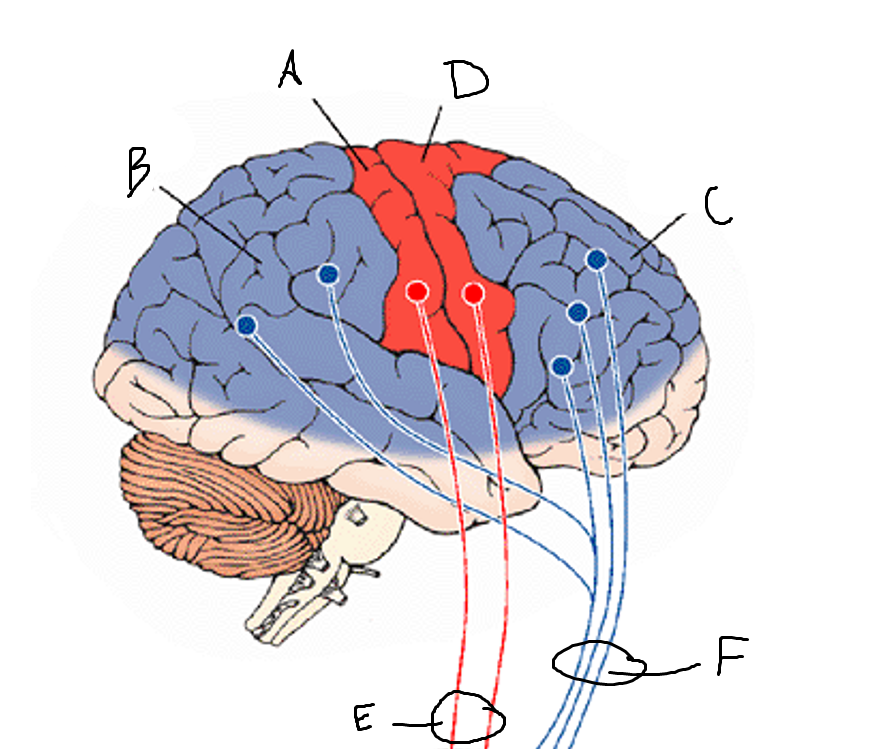

basal ganglia

A

somatosensory cortex

B

parietal association cortex

C

frontal and prefrontal cortices

D

primary motor cortex

E (where are the projections?)

putamen

F (where are the projections?)

caudate